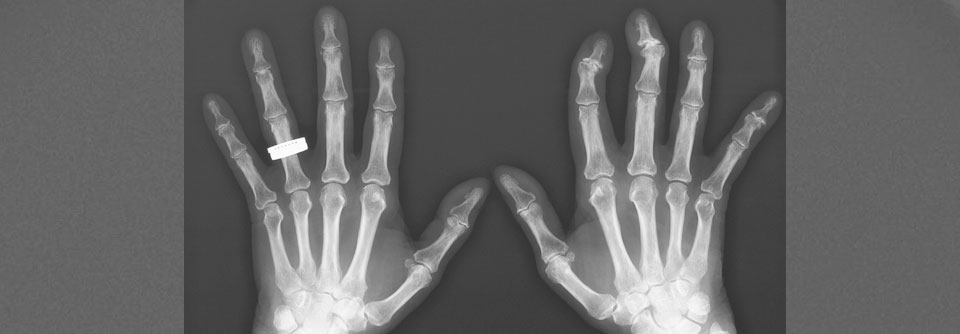

Rheumatoide Arthritis in der Hausarztpraxis diagnostizieren

Die rheumatoide Arthritis kann man oft schon in der Praxis diagnostizieren – auch im Frühstadium. Anamnese, körperliche Untersuchung, Ultraschall und…

Rheumatologie DGIM 2021